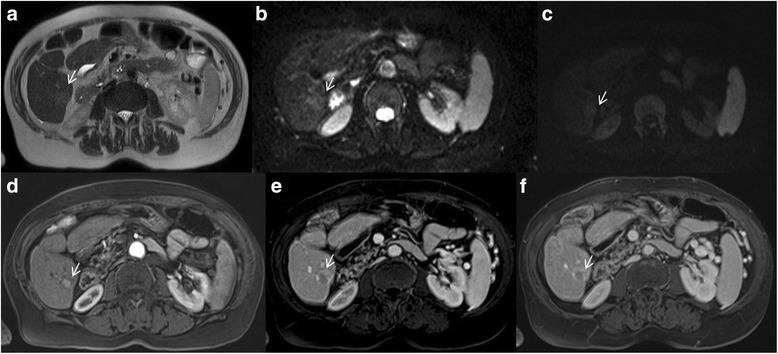

Liver Imaging Reporting and Data System (LI-RADS) is a system for interpreting and reporting of imaging features on multidetector computed tomography (MDCT) and magnetic resonance (MR) studies in patients at risk for hepatocellular carcinoma (HCC). American College of Radiology (ACR) sustained the spread of LI-RADS to homogenizing the interpreting and reporting data of HCC patients. Diagnosis of HCC is due to the presence of major imaging features. Major features are imaging data used to categorize LI-RADS-3, LI-RADS-4, and LI-RADS-5 and include arterial-phase hyperenhancement, tumor diameter, washout appearance, capsule appearance and threshold growth. Ancillary are features that can be used to modify the LI-RADS classification. Ancillary features supporting malignancy (diffusion restriction, moderate T2 hyperintensity, T1 hypointensity on hapatospecifc phase) can be used to upgrade category by one or more categories, but not beyond LI-RADS-4. Our purpose is reporting an overview and update of major and ancillary MR imaging features in assessment of HCC.

肝脏影像报告和数据系统(LI-RADS)是一种用于解读和报告肝细胞癌(HCC)高危患者多排螺旋计算机断层扫描(MDCT)和磁共振成像(MR)检查影像特征的系统。美国放射学会(ACR)推动了LI-RADS的推广,以统一HCC患者的解读和报告数据。HCC的诊断基于主要影像特征的存在。主要特征是用于对LI-RADS-3、LI-RADS-4和LI-RADS-5进行分类的影像数据,包括动脉期强化、肿瘤直径、廓清表现、包膜表现和阈值生长。辅助特征可用于修改LI-RADS分类。支持恶性的辅助特征(扩散受限、T2中等度高信号、肝胆期T1低信号)可用于将类别提升一级或多级,但不超过LI-RADS-4。我们的目的是报告在HCC评估中主要和辅助MR成像特征的概述及更新情况。